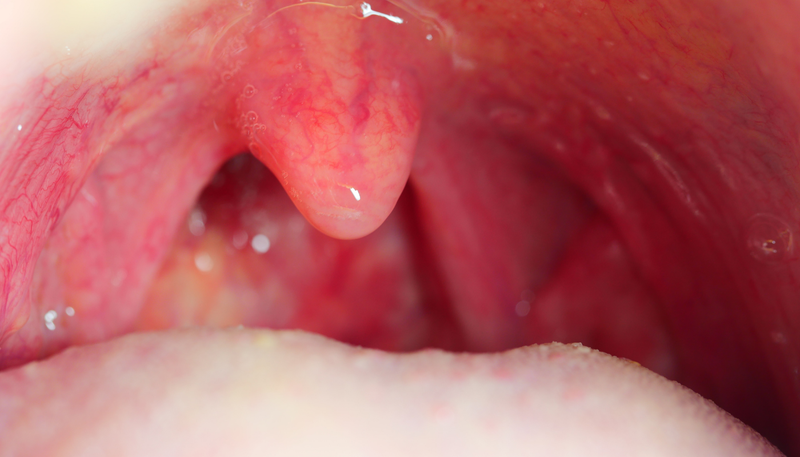

Cắt amidan là một phẫu thuật đơn giản, an toàn. Tuy nhiên, nếu không được chăm sóc đúng cách, người bệnh sẽ gặp nhiều biến chứng, từ đau họng, đau tai nhẹ đến chảy máu nặng, nhiễm trùng, phù nề lưỡi gà… Vì vậy, điều quan trọng là phải biết những điều cần tránh sau khi cắt amidan để tạo điều kiện thuận lợi cho quá trình phục hồi vết thương sau cắt amidan. Vậy sau khi cắt amidan kiêng gì để nhanh hồi phục?

Viêm amidan có thể xảy ra ở nhiều người, nhưng tỷ lệ mắc bệnh được cho là ở trẻ em cao hơn ở người lớn. Amidan là hàng rào miễn dịch của miệng và cổ họng. Khi có quá nhiều vi khuẩn tấn công, amidan sẽ bị viêm và đỏ. Nếu tình trạng viêm này bị tái nhiễm nhiều lần, khả năng chống lại vi khuẩn của amidan sẽ càng giảm đi.